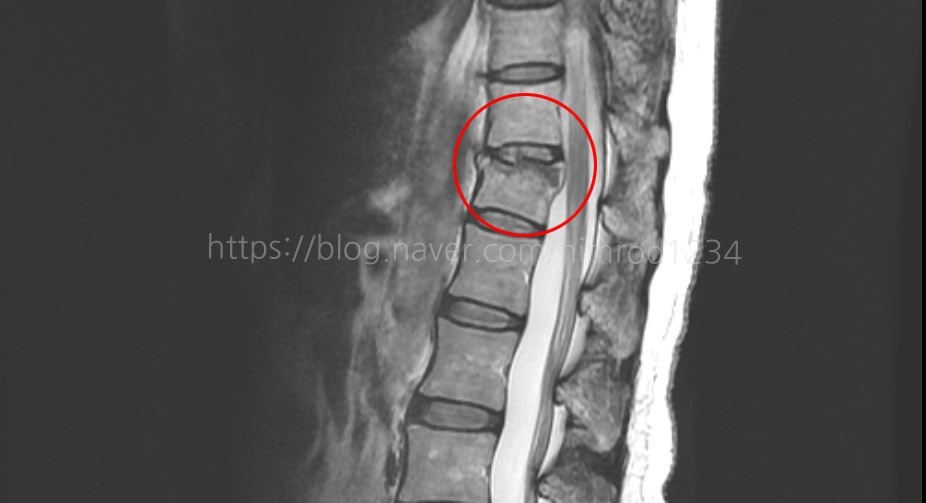

신체검사와 X-선 촬영, CT, MRI로 압박골절 유무와 정도를 확인할 수 있습니다.